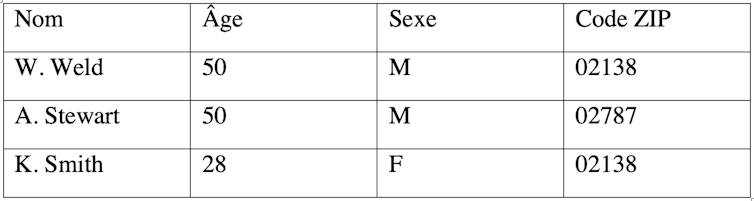

Supposons par ailleurs que nous nous soyons procurés la liste des électeurs avec leurs noms et prénoms, présentée dans le tableau 2.

Il est possible, par corrélation entre les deux tableaux, de déduire que le gouverneur W. Weld correspond à l’enregistrement #25587 du tableau 1 (et par déduction qu’il souffre d’un cancer). Cette attaque de réidentification est appelée plus scientifiquement « attaque d’individualisation ».